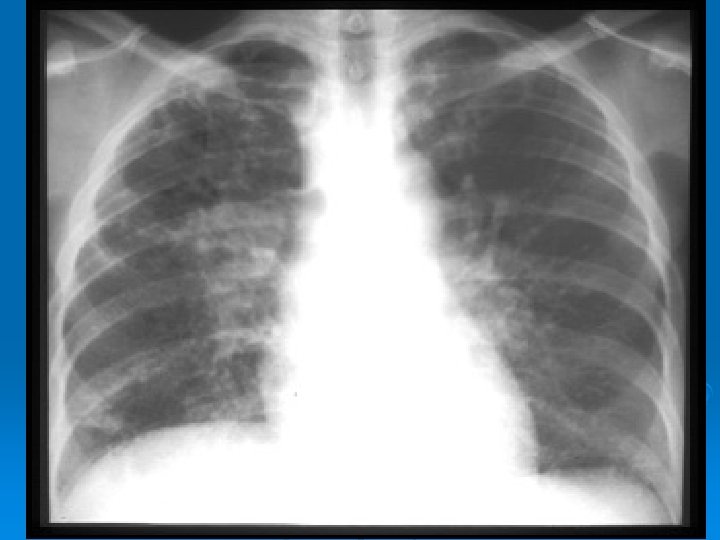

PA AKCİĞER GRAFİSİ Ø Grafiye göre evreleme yapılır: Evre 0: normal Ø Evre 1: bilateral hiler, mediastinal veya paratrakeal LAP Ø Evre 2: evre 1 + parankimal infiltrasyonlar Ø Evre 3: LAP ın eşlik etmediği diffuz pulmoner parankimal infiltrasyonlar Ø Evre 4: LAP ın eşlik etmediği fibro-kistik interstisyel akciğer hastalığı Ø

Stage II. PA chest radiograph demonstrates hilar and mediastinal adenopathy with fine nodular interstitial opacities.

Stage III. PA chest radiograph depicts diffuse bilateral reticulonodular opacities without lymphadenopathy.

Stage IV. PA chest radiograph shows fibrosis and upper lobe cystic changes and volume loss.

EVRE 4